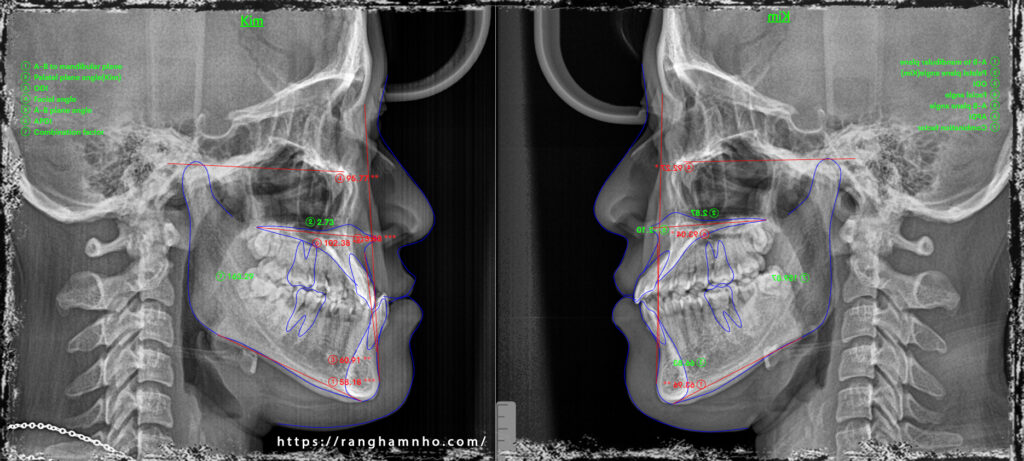

Một case sai khớp cắn hạng III góc đóng, với chen chúc cắn kéo nhiều răng. Giai đoạn san bằng và sắp đều đã được hoàn thiện trước đó. Dr Răng Hàm Nhỏ tiếp nhận và bẻ MEAW trên dây TMA 17×25 kết hợp thun 1/4 hạng III ngắn 6.5Oz trong 6 tháng. Giải quyết được hở khớp vùng răng hàm, lồng khớp hai hàm về tối ưu. Tinh chỉnh khớp cắn, duy trì và tháo niềng.

Kết quả so sánh phim chụp trước và sau điều trị.